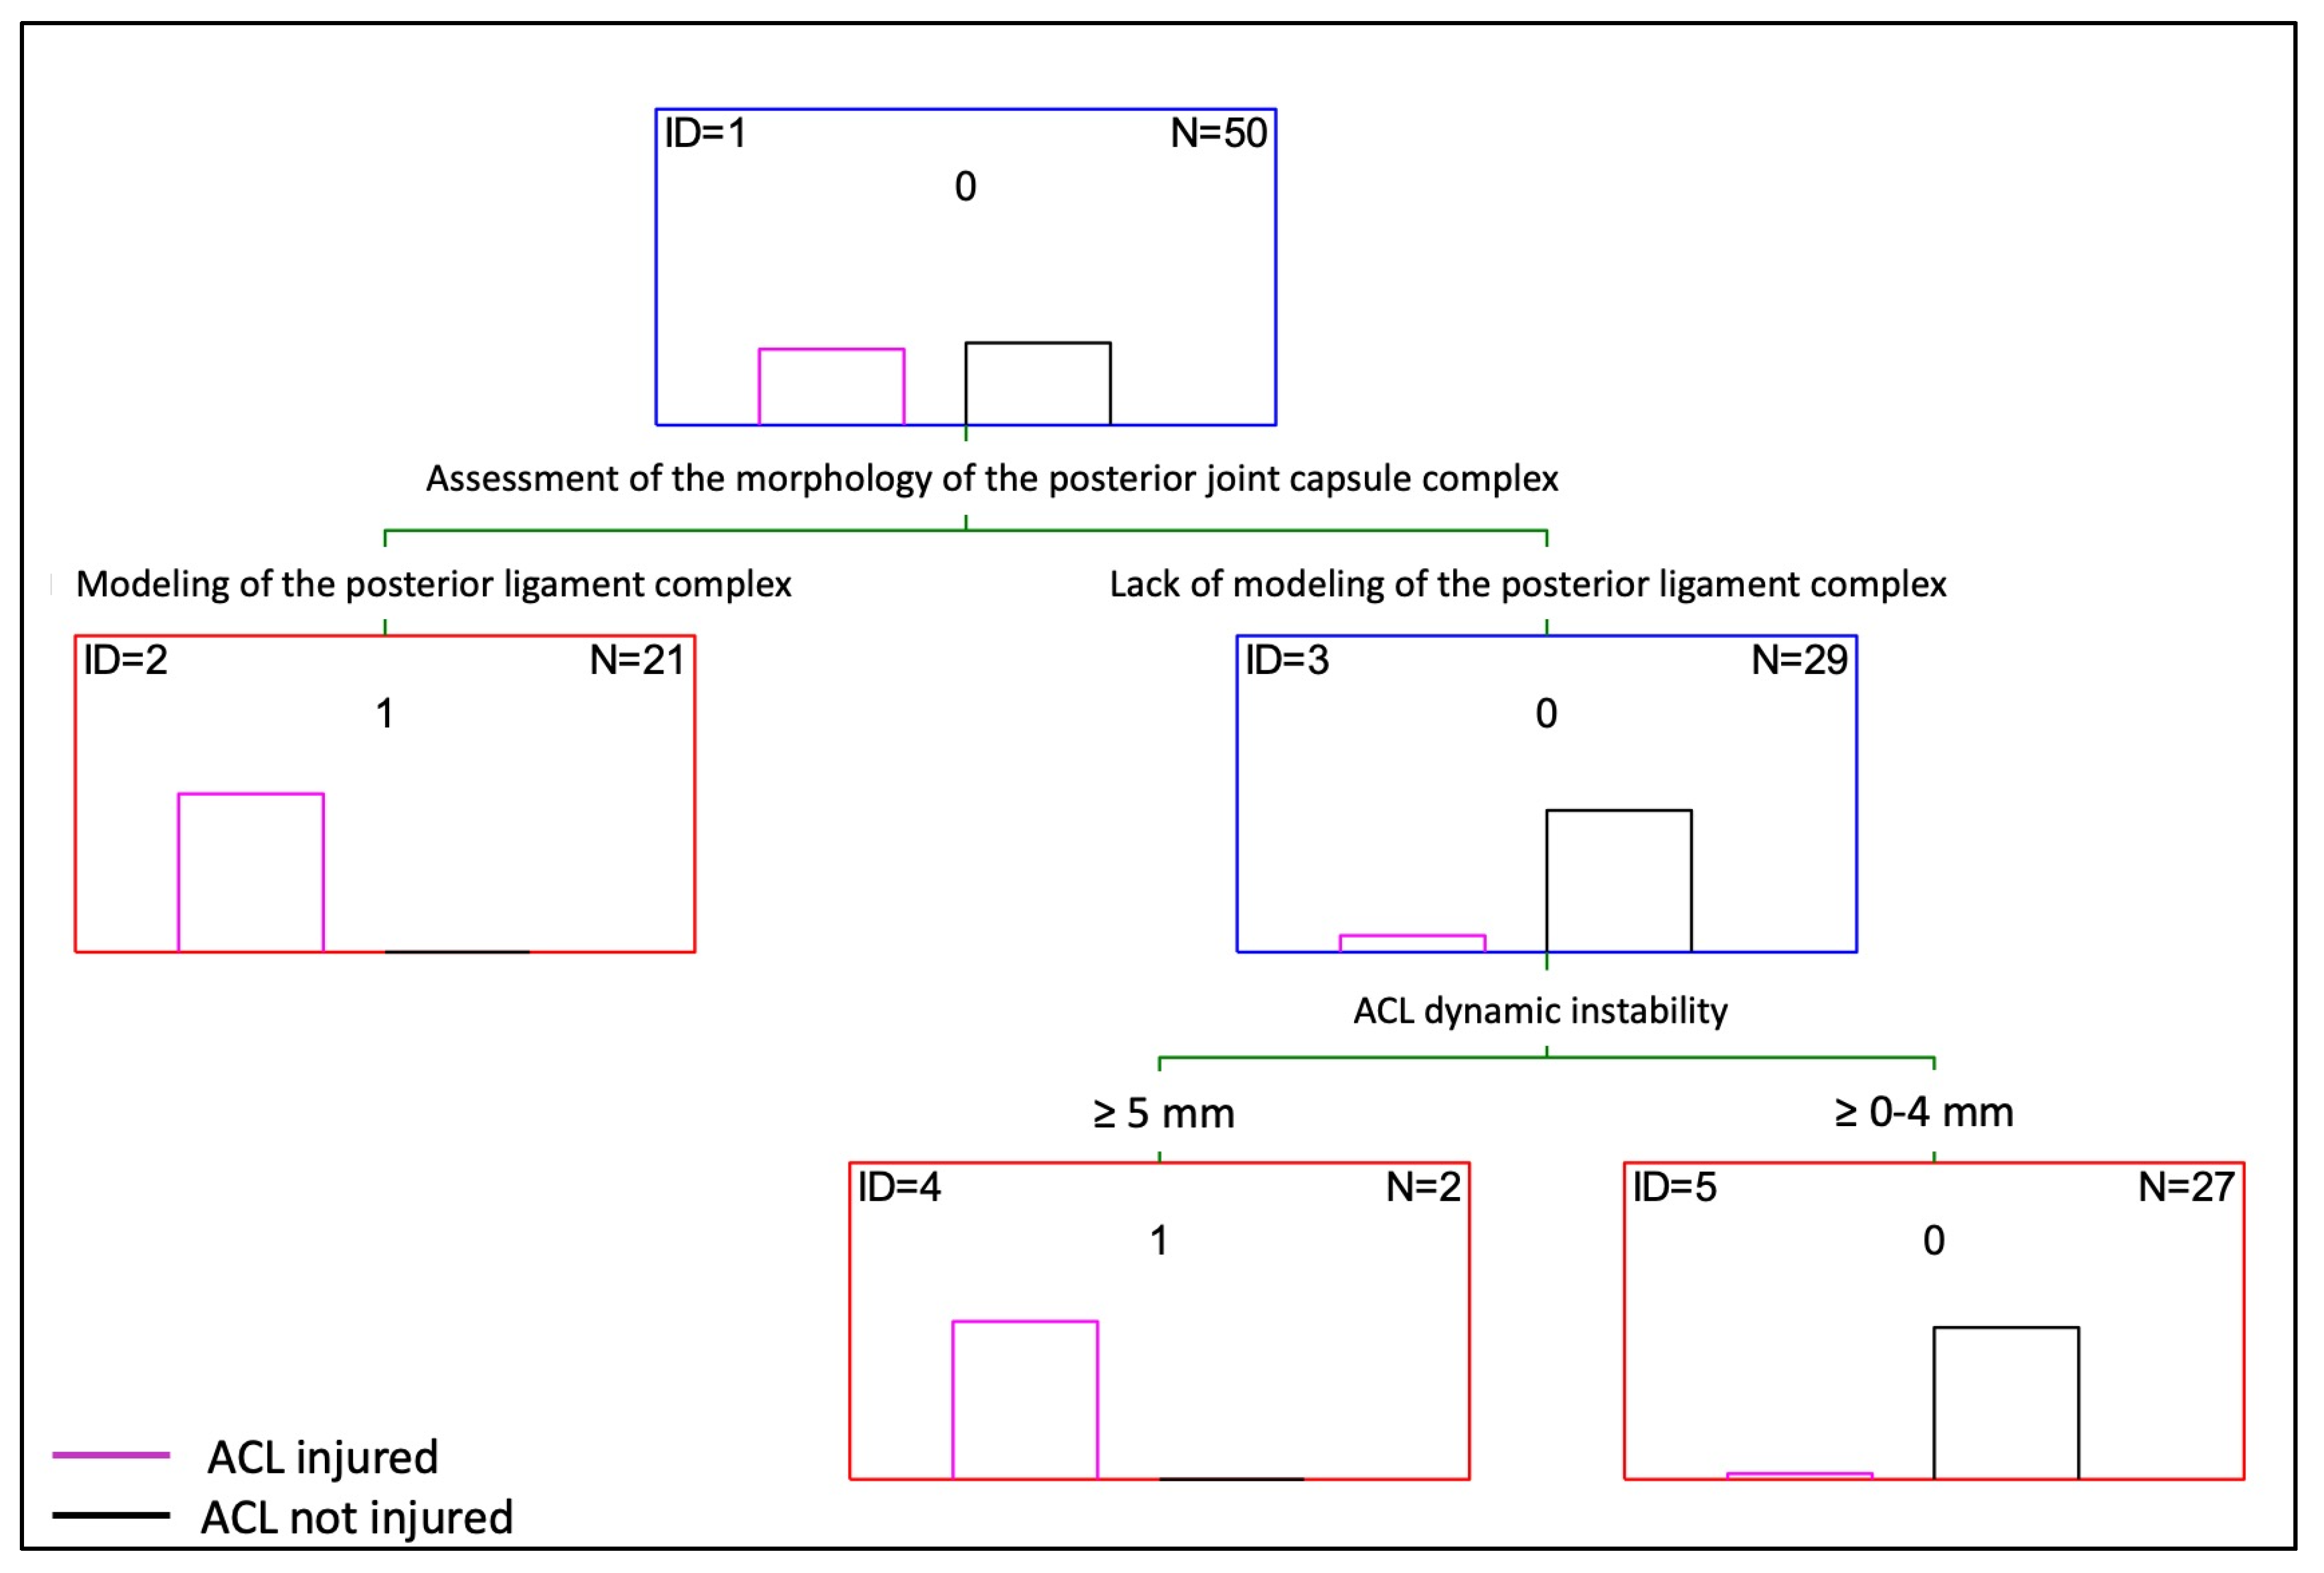

3.3. Decision Tree